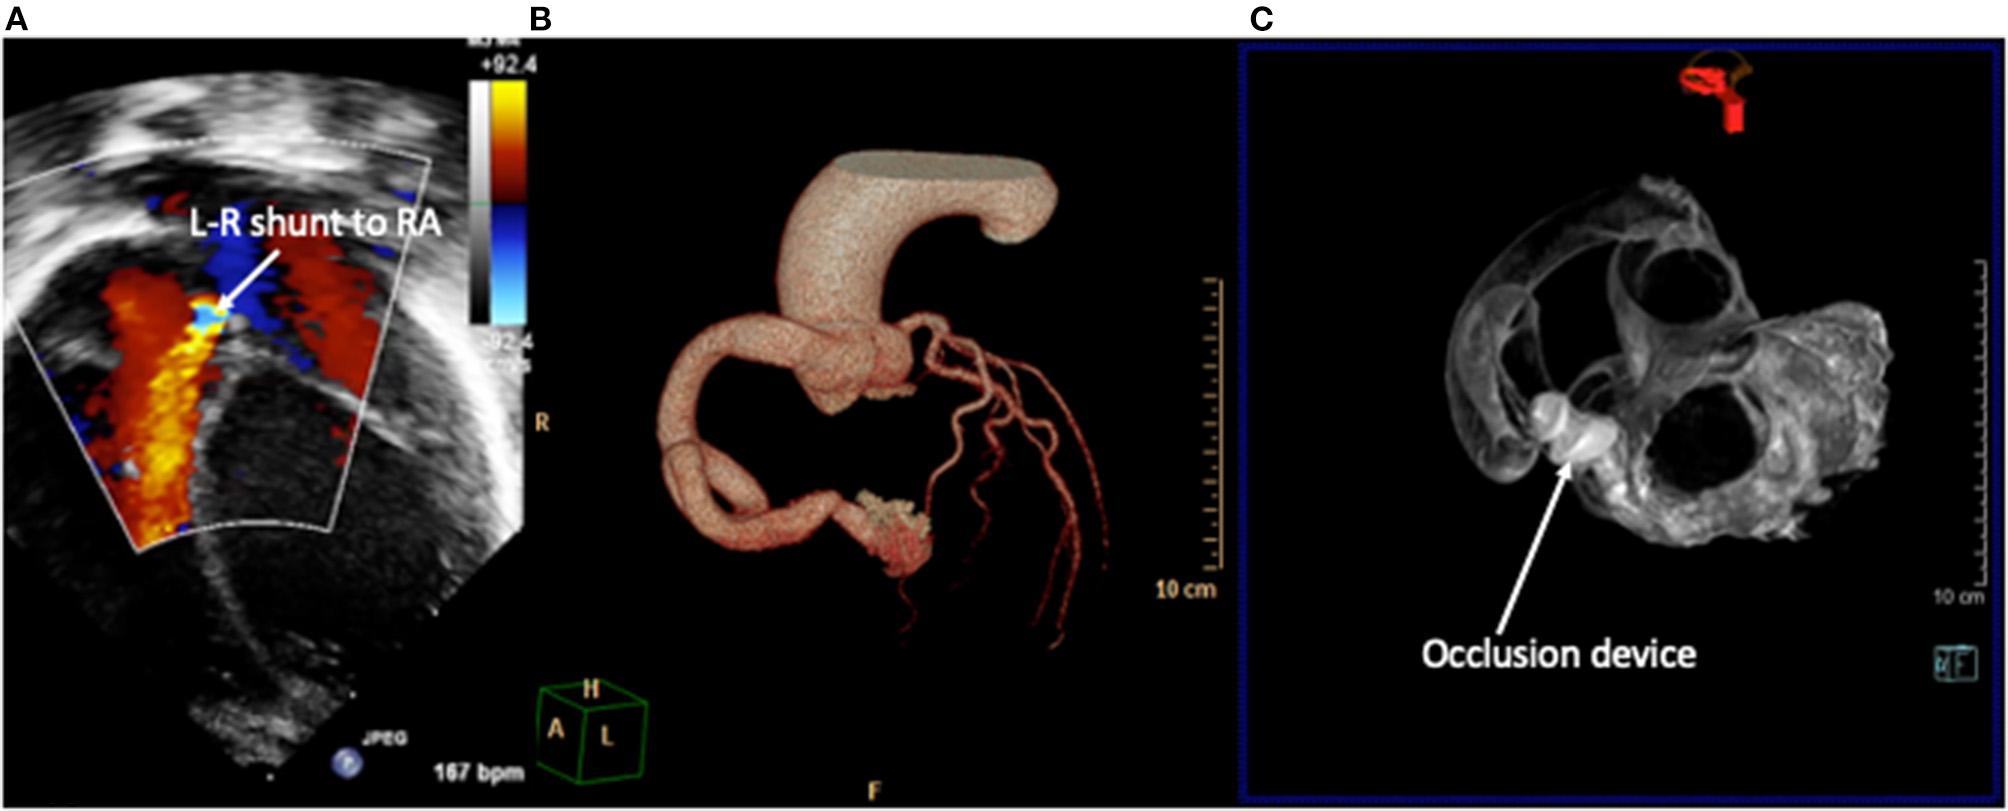

Coronary Artery Fistulae

Coronary artery fistulae or coronary cameral fistulae are an abnormality of coronary artery termination into a chamber of the heart. This can involve any coronary artery and exit sites into any cardiac chamber and have multiple feeding vessels and multiple drainage sites (48). Symptom severity depends on the degree of shunt and left- or right-heart overload. Two-dimensional echocardiography is an effective screening tool, and the origin and exit are more easily seen. The course of the defect, bends, turns, and areas of narrowing are more difficult, but dimensions of fistula can be estimated on 2D imaging. Functional assessment includes volume load, function, and estimation of the severity of the shunt. Of all (21/24), 87.5% were correctly and accurately diagnosed by echocardiography (49). The interventionalist will aim to occlude the fistula artery as distally and as close to its termination point as possible, so as to avoid any possibility of occluding branches to the normal myocardium. Where these patients previously needed invasive coronary angiography to provide detailed diagnosis, cardiac CT is the preferred imaging modality and can be used to produce 3D models to the evaluation of suitability for interventions (31) (Figure 6) to help define the site, size, and potential landing zone for the occlusion device(s) without risk of embolization or occlusion of important coronary connections.

Figure 6

Right coronary artery fistula to right atrium (RA). (A) 2D echocardiography with color Doppler demonstrates the drainage point of the fistula into the RA at high velocity. Images courtesy of Israel Valverde, King's College London. The course of the fistula is better defined on contrast-enhanced CT (B) which allows for simulation of device occlusion as shown in a rotational CT image in image (C).